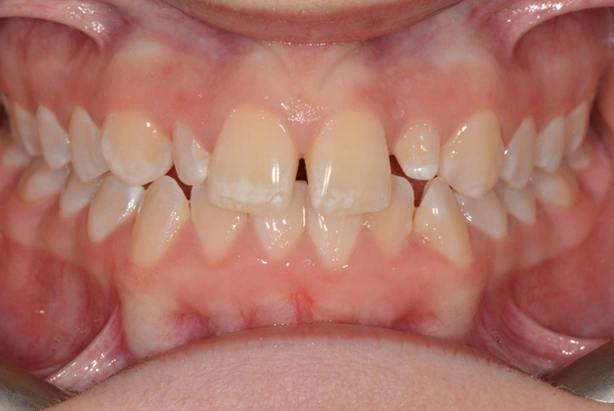

Peg Shaped Laterals

Diminutive lateral incisors are one of the most common problems we see. After careful assessment with patient, parent and referring dentist, it was decided to complete full fixed appliance treatment with space creation for composite buildups of the 12 and 22.

Alignment and occlusion were perfected and the patient referred back to dentist to approve of space distribution.

Appointments were coordinated so that all appliances were removed in the morning. Build-ups undertaken around lunch and final retainers issued by the end of the day.

A great result. With potential permanent indirect restorations after growth completed if needed.